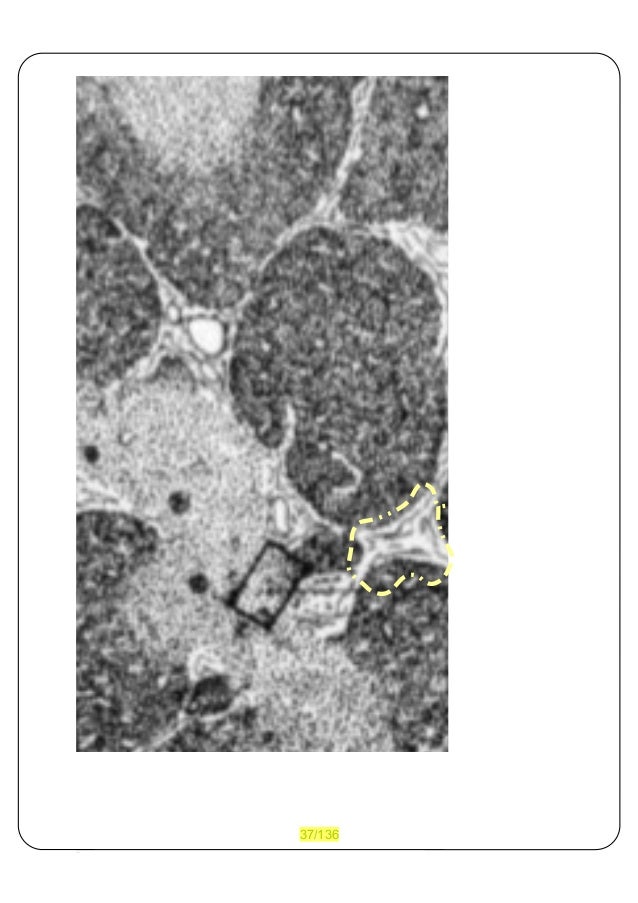

36. 36. BeurO Germini_Colombo via G.Brufani 18 06124 PG_I Dott(2°).Ing.Arch.giovanni Colombo A1360 PG_I_1995 09171 B_de_2003_2011 IVA_nr.:02819100542 A) che gli distinti organi secernenti gli Globuli bianchi ed trasparenti per arrivare ad ogni punto del corpo vanno DISSEMINATI loro stessi, B) ogni degli organi secernitori è specializzato secondo criteri sia di linfociti che di macrfagi specializzati, per cui illoro diffondersi avviene prevalente per grandi distanziali tramite sistema cardiovascolare. Gli organi predisposti si chiamano organi secretori, dette anche ghiandole ed queste, vengono descritte come: adenoidi, che vicino setto nasale, tonsille vicino alla mascella ed trachea, milza che trovasi accanto all'intestino zonato ad sinistra, timo che trovasi vicino allo sterno, ecc.... tra questi gli più diffusi sono gli linfonoidi, che trovasi anche ad esempio sotto le ascelle, spesso quando avete un influenza si possono lieve gonfare ed questo esprime che il loro aumento di sintetizzare sistema immunitario aumenta, ..od facile da rilevare e' anche dietro al collo che sembrano dei noccioli d'olive... quivi è riportato un istologico rilievo di: Thymushistologie – Übersichtsvergrößerung aus: O. Bucher, H. Wartenberg: Cytologie, Histologie und mikroskopische Anatomie des Menschen Verlag Hans Huber; 11 Auflage; 1992, che rappresenta il timo uno degli organi secretori il nostro sistema immunitario.

37. 37. 37/136 ed che T

39. 39. Secondo come esplicato quivi di seguito il circoscritto giallo tratteggio corrisponde, ad liquidi che isolano interi agglomerulati cellulici come sospesi su liquido: il fluido interstiziale.... anche se è errato come semplicizzato... Thymushistologie aus: O. Bucher, H. Wartenberg: Cytologie, Histologie und mikroskopische Anatomie des Menschen Verlag Hans Huber; 11 Auflage; 1992; 7 = Epithelzellen im Mark; 8= Hassall Körperchen; 6= Venole an der MarkRindengrenze; 2, 5= eosinophiler Granulozyt; 4= Epithelzellen in der Rinde; 3= TLymphozyten; 1 = interlobuläres Bindegewebe 39/136 ed che T